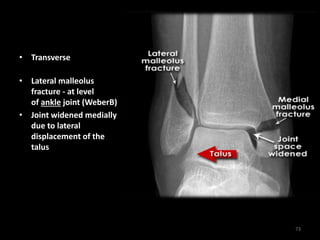

Bimalleolar fractures - AP

• Transverse medial

malleolus fracture

• Lateral malleolus

fracture - at level

of ankle joint (WeberB)

• Joint widened medially

due to lateral

displacement of the

talus